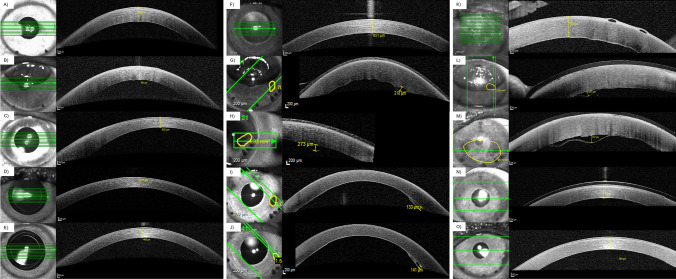

Graft detachment was defined as a gap between the donor graft and the recipient corneal stroma observed in slit lamp examinations and confirmed via AS-OCT (Fig. 1; Spectralis-OCT, Heidelberg Engineering GmbH, Heidelberg, Germany). The area of detachment was encircled in the en face images using the Spectralis-OCT software, as seen in Fig. 1M. By dividing the encircled area of detachment by the total graft area, the proportional detachment was obtained. Graft detachments were subdivided into minor (< 1/3 of the graft) or major (≥ 1/3 of the graft) detachments, with a subsequent indication for a rebubbling (Fig. 1). A successful rebubbling was defined by a complete graft reattachment at the next follow-up. In a modified classification based on the work of Coco et al., the degree of posterior stromal ripples was graded as none, mild, or severe based on their number (0 for none, ≤ 4 for mild, or > 4 for severe) as presented in the single most central cross-sectional AS-OCT image (parameters in Spectralis-OCT: 20° × 10°, 512 A-scans, 41 sections at 139-µm width), as seen in Fig. 2 [22]. To match the term used in the original publication by Coco et al. firstly addressing the appearance of corneal ripples and their relevance for DMEK graft detachments, we choose to use the term posterior stromal ripples, instead of the also commonly used term stromal folds.

Fig. 1.

Central corneal thickness (CCT), area of detachment, and maximum distance of detachment measurements prior to, 1 day, 1 week, 1 month, and 6 months after Descemet membrane endothelial keratoplasty (DMEK) via anterior segment spectral-domain optical coherence tomography (AS-OCT, Heidelberg Engineering, Heidelberg, Germany). A–E No detachment. F–J Graft detachment < 1/3 of graft area. K–O Graft detachment ≥ 1/3 of graft area with subsequent rebubbling. M: Encircled area of detachment in the en face image on the left. Proportional detachment ≥ 1/3 of the graft’s area